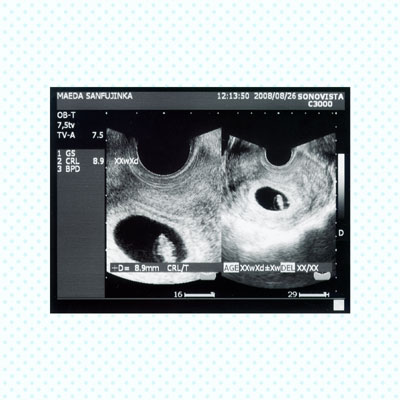

エコー写真ページ

エコー写真をお入れします。

エコー写真ページ・コメントあり

コメントを追加する場合は、1コメントごとに30円かかります。

文字数に制限はありませんが30文字ほどが適当です。

それ以上の文字数も可能ですが文字数が多すぎですと文字のサイズが小さめになりますのでご注意ください。